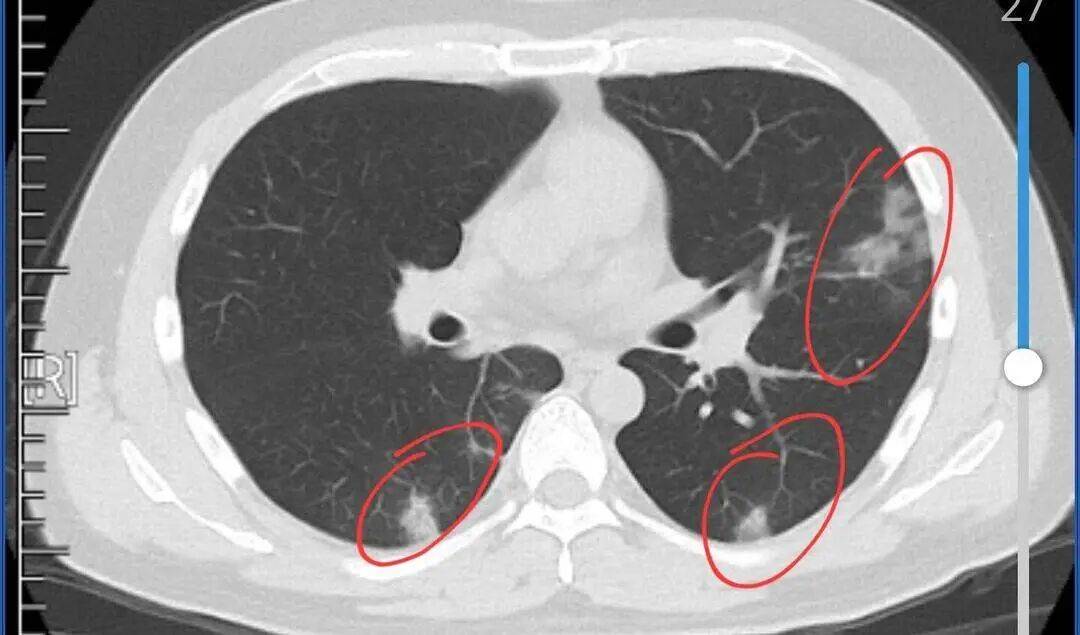

征兆三:结节密度增加

在进行定期的肺部检查时,如果你发现自己的结节密度明显增加,这同样是一个不容忽视的信号。密度的增加可能意味着结节内部的结构正在发生变化,这种变化往往与癌变息息相关。